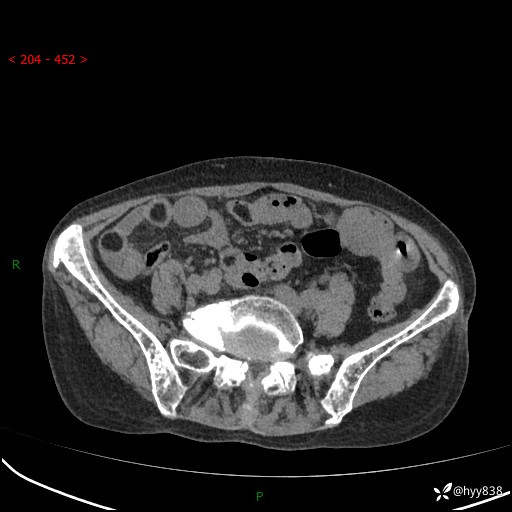

全腹部CT平扫